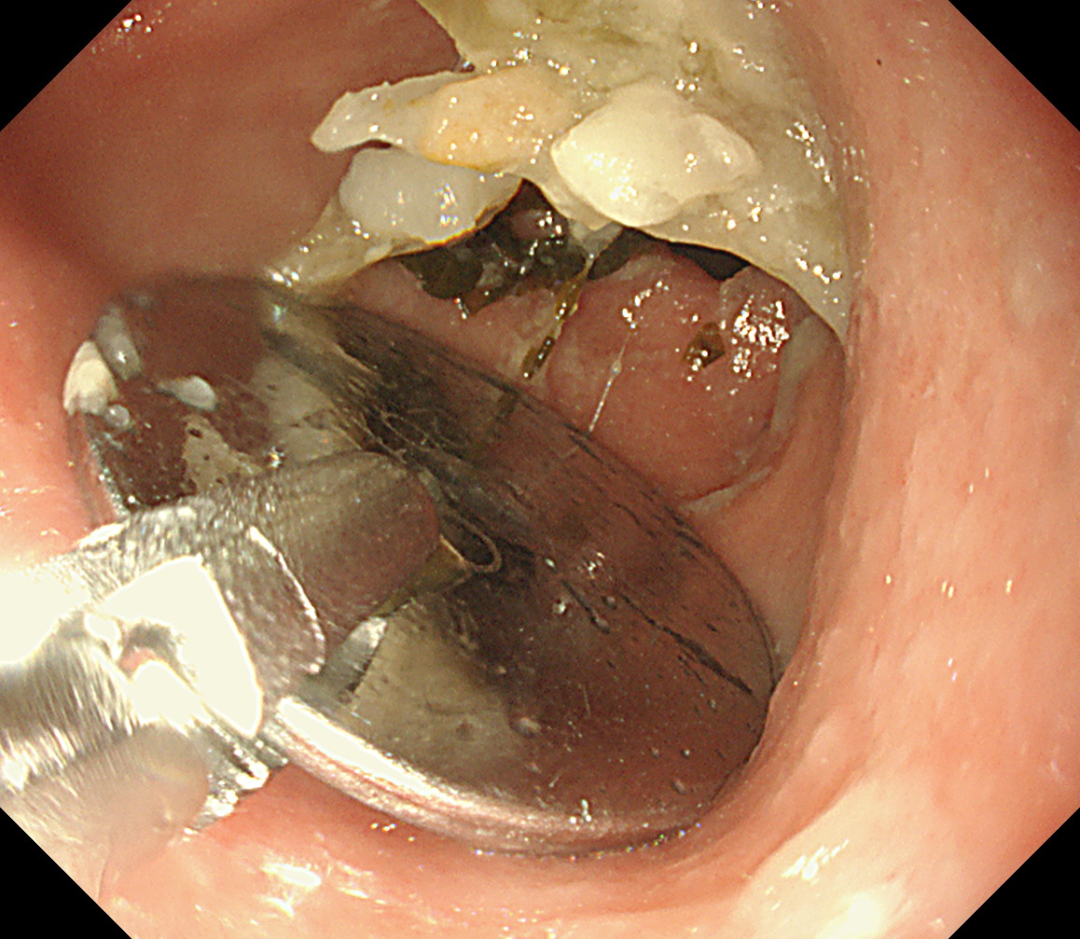

在無痛胃鏡的幫助下,手術團隊在小女孩的胃裡(lǐ)找到了那個硬币大小(直徑約1.5cm)的電池,卡在了幽門口,還(hái)好(hǎo)沒(méi)有進(jìn)入小腸。

醫生們用異物鉗小心翼翼地將(jiāng)電池取了出來,這(zhè)一刻,所有人的心都(dōu)放下了一塊大石頭。